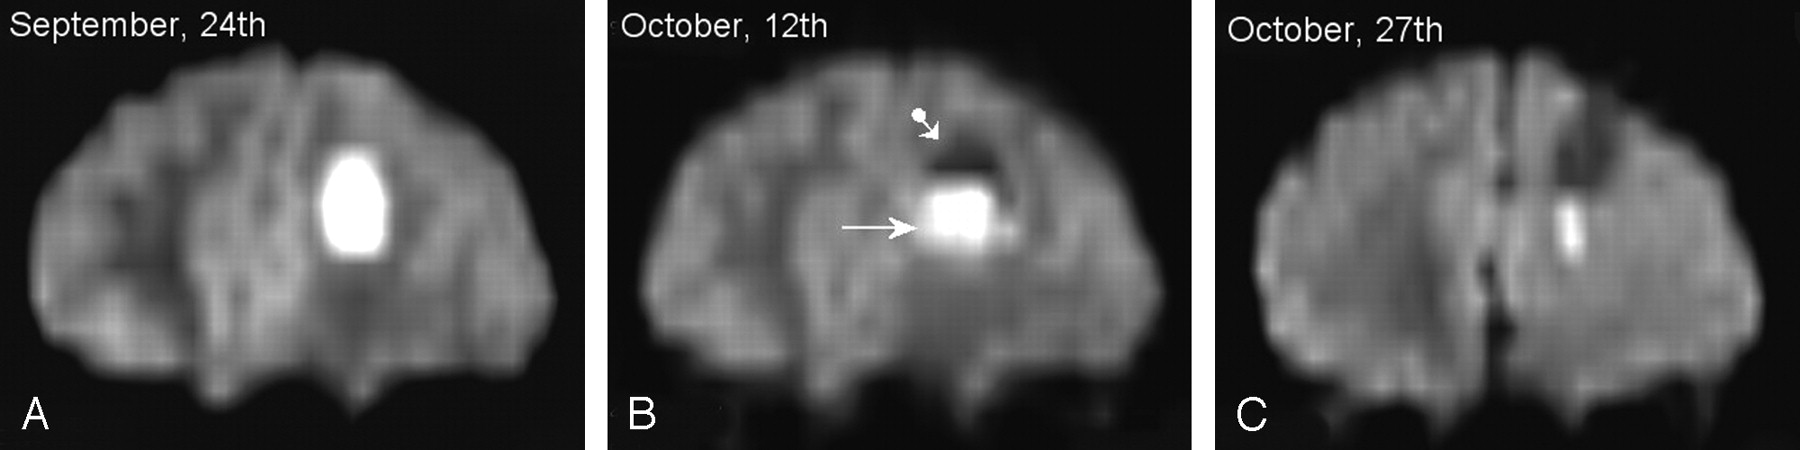

A few years ago, we published the observation of a 14-year-old boy presenting with a pyogenic frontal brain abscess brain that was not immediately treated surgically and showed two components that evolved with time on serial DW images (3). Newly reformatted images of this case are shown in Figures 1 and 2. The patient presented with a febrile meningeal syndrome and biologic markers for sepsis. We observed a strong time dependence of both signal intensity and apparent diffusion coefficient (ADC) values of the abscess throughout serial DW image monitoring. In the initial phase of the disease course a hyperintense material completely filled the abscess cavity, in which the ADC was decreased when compared with contralateral normal brain tissue (Figs 1A, 2B). The strong hyperintensity in the homogeneous core was thus far prominently due to true diffusion-weighting because only moderate hypersignal intensity was observed on corresponding T2-weighted images (Fig 2A). Shortly after the initiation of empirical antibiotic therapy, a sharply delineated hypo-/hyperintense interface between pus sediment and fluid supernatant appeared (Fig 1B). The ADC values of the hyperintense component had then become slightly elevated when compared with normal brain tissue, thereby suggesting the prominence of the T2-weighted shine-through effect in the hyperintensity of the lesion (Fig 2D). Delayed stereotactic drainage confirmed the presence of thick pus containing neutrophilic pyocytes but failed to identify the causative organism. A second follow-up examination after drainage revealed further shrinking of the hyperintense component (Fig 1C).

Patient 1. Frontal reformats of serial DW trace images.

A, Status at admission: complete filling of the abscess cavity by hyperintense material. Hyperintensity was mainly due to true diffusion weighting effect (see Fig 2A, -B).

B, Status 3 weeks later: appearance of two components with a sharply delineating interface. Hyperintensity at the time was mainly due to T2-weighted shine-through effect (see Fig 2C, -D).

C, Status 5 weeks later: further decrease in size of the hyperintense component after stereotactic drainage. The patient had clinically recovered at the time.